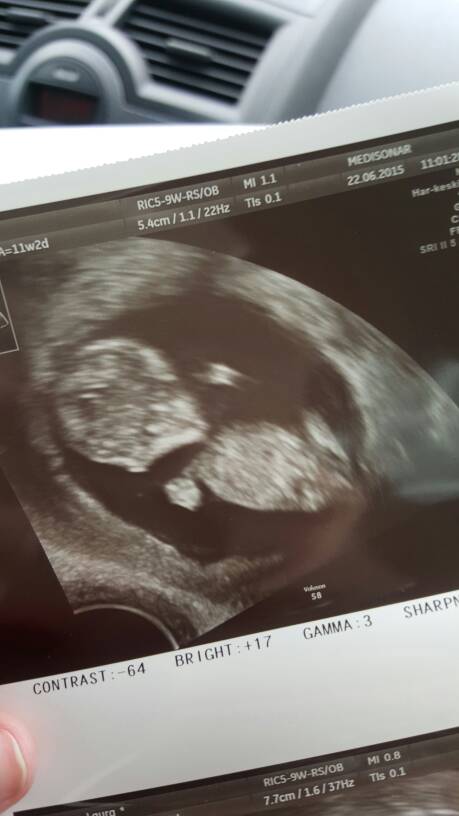

Meidän rakas <3 rv 11+2, vastasi viikkojaan ja niskaturvotus oli erittäin hyvä :) eli ei aihetta huoleen !

Liitteet

• 1434962258234.jpg

1434962258234.jpg

34.1 KB · Katsottu: 193

Onnea lauruskaah! Siellä se pieni polskii! :) <3

Lauruskaah,ihania ultrakuulumisia,onnea!